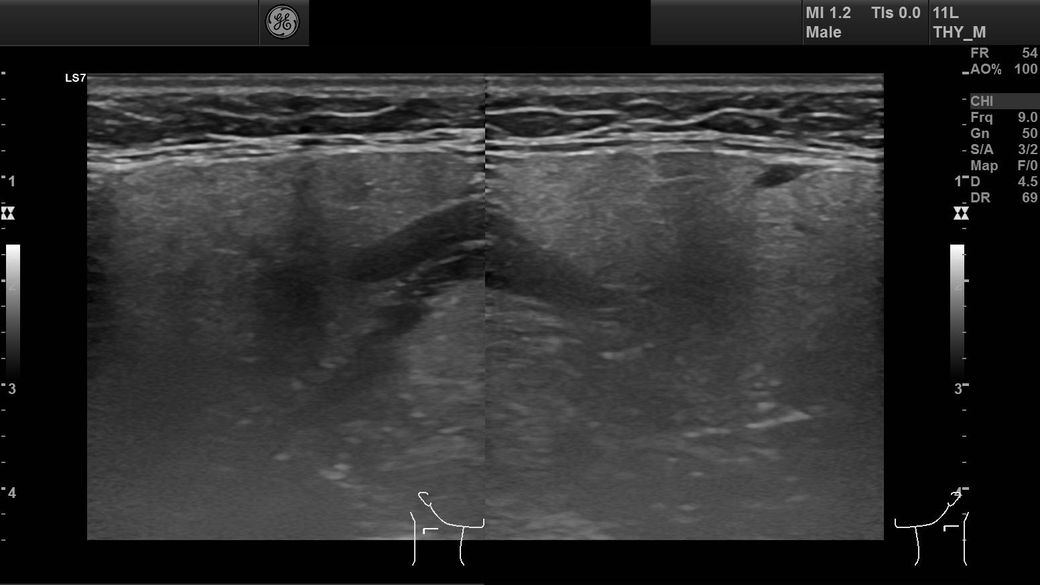

경부초음파사진 결과 사진 질문드립니다

임파선이 부어서 초음파를 찍었는데

어떤 사진인지는 모르겠는데 혈관이 왼쪽에 비해 오른쪽이 좁다고 하셨는데 이게 큰 문제가 있는건가요?

• 2번 째 사진

혈관이 좁다고 했다면 경동맥을 말하는 것 같습니다

경동맥의 경우 2D로 관찰을 했을 때 내강이 절반이 되더라고 전체면적으로 봤을 떄는 많이 좁아진 것이 아니니

크게 걱정하지 않으셔도 됩니다

판독기록에 어느 정도 좋아졌는지 확인을 해보세요